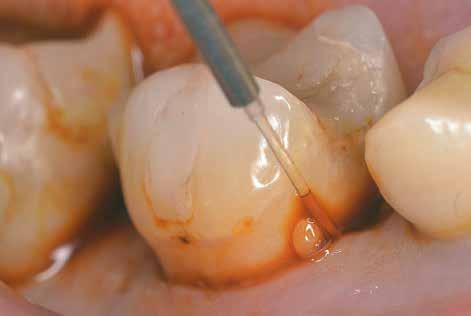

A cikk szerzőjének rendelőjében végzett kezelések során egy AIR-FLOW Master Piezon homokfújó készüléket (EMS; 6. ábra) és 0,3% klórhexidint tartalmazó erythritol port (AIR-FLOW PLUS powder, EMS; 14 μm-es átlagos szemcseméret) használnak a subgingiválisan elvégzett homokfújás során. A beavatkozás elvégzéséhez egy speciális thermoplasztikus elasztomerből készült, egyszer használatos csőrt alkalmaznak (7. ábra)

A levegő-por keverék az előbb említett csőrből horizontális irányban távozik, míg a folyadék a csőr végén elhelyezke-

dő nyílásból lép ki, és a fogak felszínének mechanikus módszerekkel történő tisztításával egyidejűleg, 5 má sodpercen keresztül a parodontális tasakot is átöblíti. Miután a AIR-FLOW Master Piezon készülékkel törté nő homokfújást befejeztük, megkezdjük az ugyaneh hez a készülékhez tartozó, ultrahangos depurátorral történő kezelést (8. ábra). A fent említett beavatkozá sokat általában helyi érzéstelenítés alkalmazása nélkül végezzük el.